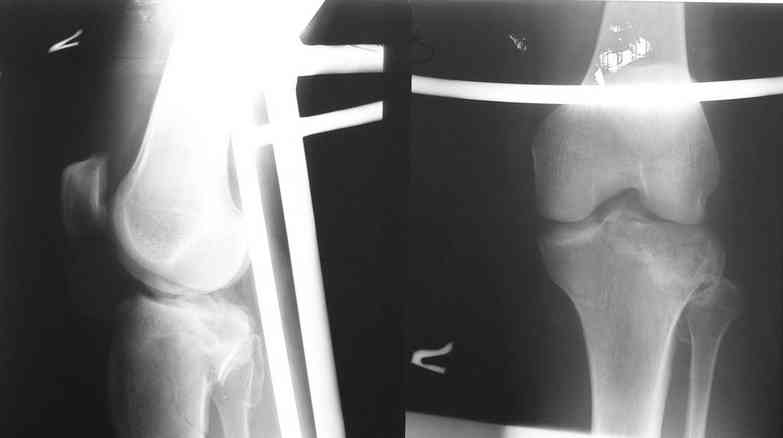

Уважаемый Леонид! Вы имеете дело с переломом Tibial plateau. Для того, чтобы можно было классифицировать перелом, представленных снимков КТ не достаточно, поэтому, если можно дайте снимки рентгеновские обыкновенные.

Скорее всего у Вашего пациента Бикондилярный перелом проксимальной тибии с депрессией латерального тибиального плато.

Спасибо за ответ высылаю R- граммы пациента. Ранее как и в это раз оперировали открыто репонируя суставную поверхность из дополнительного окна по передней поверхности мыщелка дефект губчатой ткани заполняли аутотрансплантатом с гребня подвздошной кости или пористым никелид титаном и фиксировали мыщелковой пластиной. В данном случае межмыщелковое возвышение фиксировали проволочным швом окно для поднятия суставной поверхности сформировали по передне-наружной поверхности н/мыщелка, дефект заполнили аутокостью и фиксировали пластиной с угловой стабильностью с болтом-стяжкой. В ближайшие дни покажу контроль R-гр, КТ.